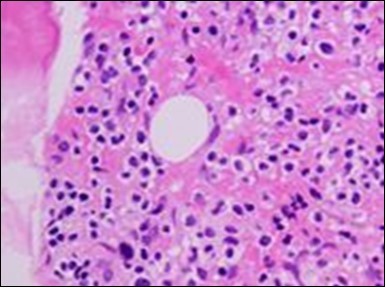

The leukaemia cells may enunciate a characteristic immune phenotype, crucial for a confirmatory diagnosis. The peripheral blood mononuclear B cell population may display a kappa or lambda light chain restriction. The phenotype of classic hairy cell leukaemia may be delineated by concurrent, immune reactive CD19+ CD20+,CD 11c+, CD25+, CD103+ and CD123+. An intensely immune reactive CD200+ and a non reactive CD27- antigen may be present2, 4. Evaluation of a trephine bone marrow biopsy and bone marrow aspirate may define the degree of tumour infiltration. A dry tap on account of prominent bone marrow fibrosis may be elucidated at preliminary diagnosis. A decline in the normal haematopoiesis may account for a hypo-cellular marrow in 10% instances. Gradation of cellular infiltrating of the leukaemia within the bone marrow may be appropriately investigated with immune –histochemical stains2, 4. Immune staining for CD20+, annexin 1 and VE1 (a BRAF V600E stain] may validate the diagnosis and precisely analyse the extent of malignant bone marrow infiltration[8]. Determination of BRAF V600E mutation may be critical in therapeutically non responsive individuals with applicable standard therapy or in instances of multitudinous reoccurrences[9]. Deploying inhibitors of BRAF V600E gene may be efficacious in patients impervious to approved therapy. The mutation necessitates a comprehensive scrutiny of the implicated individuals with a sensitive molecular assay which may discern up to < 10% of the hairy leukaemia cells appearing in the peripheral blood smears or bone marrow aspirates diluted with peripheral blood or aspirates elucidating a dry tap[2,4]. Allele specific polymerase chain reaction (PCR) or a next generation sequencing may be optimally employed to circumvent false negative outcomes. If the leukaemia cells are sparse or if particularly sensitive & efficacious molecular techniques are not accessible, the application of appropriate immune histochemical stains to the bone marrow biopsy such as a BRAF V600E mutation stain (VE1) may detect the hairy cells and conclusively diagnose the condition[2,4,10]. Figure 1, Figure 2, Figure 3, Figure 4, Figure 5, Figure 6, Figure 7, Figure 8, Figure 9, Figure 10, Figure 11, Figure 12, Figure 13, Figure 14.

Figure 2.HCL: hairy cells with projecting cytoplasm abutting bony trabaculae(18).

The classic hairy cell is medium sized with a magnitude of 10-14µm. The moderately abundant or variable cytoplasm may be transparent or mildly basophilic. The cellular surface with the characteristic serrated perimeter depicts innumerable fragile or stout extensions of cytoplasm ,particularly discernible on the phase contrast and electron microscopy. The cytoplasm may exhibit vacuoles with occasional azurophilic granules4. The nucleus may be elliptical or reniform, folded or indented with a coarse, reticulated or a finely dispersed chromatin and inconspicuous nucleoli along with infrequent mitosis. Bone marrow aspiration or bone marrow trephine biopsy may be inadequate for diagnosis in 30%-50% individuals4. The trephine sections of the bone marrow may depict a characteristic interstitial pattern of leukaemic infiltration. Generally the bone marrow is hyper-cellular, though it may be hypo-cellular in 10-15% individuals4. The leukaemia cell ingress may be diffuse or partial, although diffuse infiltration is frequent. The partial variety of leukaemic dissemination may be ineptly categorized with an indeterminate differentiation from the uninvolved marrow. The malignant insertions may initially emerge as miniature, undefined, cellular loci. The formalin fixed, paraffin embedded sections may elucidate a crystalline zone or a “halo” appearance of the cells with a circumscribed nucleus on account of the plentiful cytoplasm4. The cellular margins may be intertwined. Fixation of bone marrow smears with Zenker’s fixative may demonstrate a retracted cytoplasm of the hairy cells with a consequent disconnected structure. The bone marrow in the absence of a malignant process may be hypo-cellular or hyper-cellular. Reticulin stains may delineate an enhanced accrual of broad, dense reticulum fibres surrounding the aggregates of leukaemia cells with the fibrous circumlocution of individual malignant cell and fibrotic extensions into the abutting, uninvolved bone marrow4.